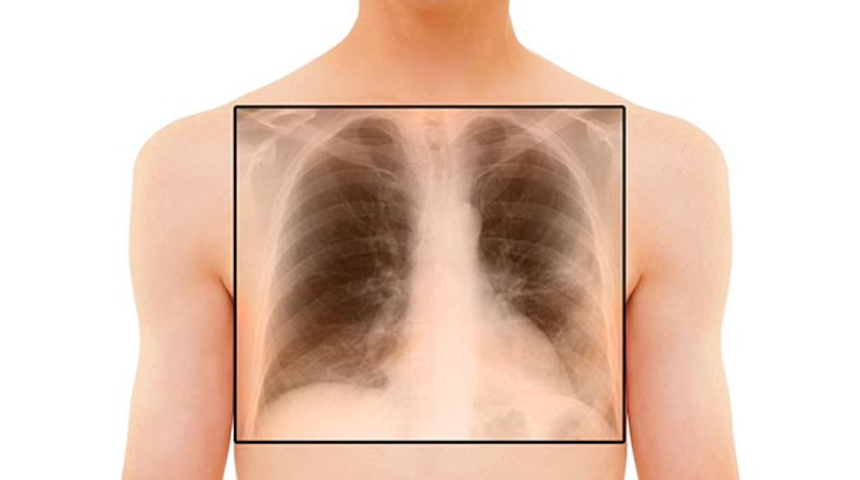

BOOP'da, akciğer röntgeninde çoğu zaman iki taraflı beyazlaşmalar vardır; nadiren tek bir lezyon da olabilir. Akciğer tomografisi ile bu bulgular daha iyi belirlenebilir, ancak yine de zatürre ya da akciğer kanseri gibi hastalıklardan kesin olarak ayrılması mümkün değildir. Solunum fonksiyon testlerinde, akciğer kapasitesinin azalmış olduğu saptanır, ancak astımlılarda olduğu gibi bronşlarda daralmaya at bulgular yoktur. Kanda oksijen ve karbondioksit basınçları azalmış olarak bulunur.